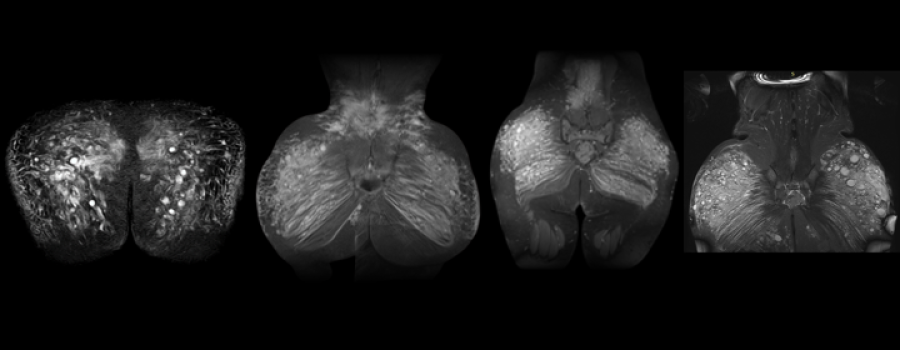

Este artículo buscó mapear (ubicar anatómicamente) cómo quedan distribuidos los biopolímeros en pacientes que consultaron para cirugía de retiro, usando hallazgos de RMN sin contraste.

La resonancia magnética (RMN) es fundamental en el proceso de extracción de biopolímeros, porque permite identificar con exactitud la localización, volumen y nivel de infiltración de los biopolímeros en los tejidos.

Hablar de los casos reales tratados en el artículo: “Fue un estudio retrospectivo: revisaron casos reales de pacientes que ya habían sido valoradas con resonancia. Incluyeron 286 pacientes, evaluadas entre 2017 y 2024, y usaron un protocolo de RMN simple con secuencias estándar (STIR, T1, T2).

Hallazgo #1: Casi nunca está en un solo punto

Cuando dividieron los glúteos por cuadrantes, encontraron algo muy diciente: casi todas tenían compromiso de todos los cuadrantes. O sea: el material no se comporta como una ‘bolita localizada’.

• Compromiso prácticamente universal de cuadrantes: 97.2%

• Cuadrante superior externo: 99%

• Multirregional (≥3 regiones glúteas): 73%

Hallazgo #2: A veces también compromete músculo

Además de tejido superficial, en muchos casos había hallazgos que sugerían compromiso muscular, especialmente del glúteo mayor.

• Glúteo mayor comprometido: 87.4%

• Glúteo medio: 4.2%

• Tensor fascia lata: 3.5%

Hallazgo #3: Los biopolímetos pueden migrar fuera del glúteo

Un punto muy importante del artículo: también describen migración hacia zonas extraglúteas. Esto ayuda a entender síntomas, molestias o hallazgos que a veces ‘no cuadran’ con lo que la persona cree que tiene.

• Región lumbar: 32.2% (frecuente en L4–L5)

• Fosa isquioanal: 23.4%

• Cadera: 13.3%

• Muslos: 12.2%

• Inguinal: 7.4%